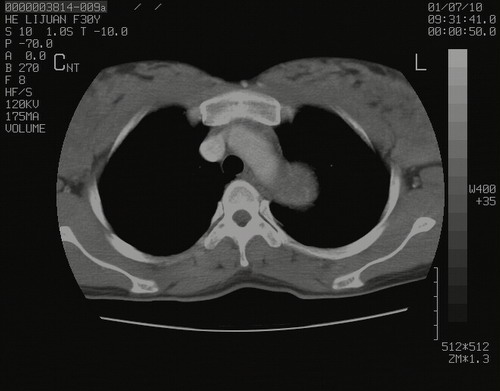

怀孕3个月时(2009-3至4月间),自述突感左侧前后胸疼痛1天,以前胸明显,随后偶感闷痛,余未见异

左肺尖脊柱旁沟肿块,境界清楚,边缘光滑,密度不均,内有多发点片状钙化,考虑良性肿瘤,骨软骨瘤或神经源性肿瘤可能,肺错构瘤不除外。

左后上纵隔见一类圆形肿块影,外侧边界清,密度不均匀,内可见点状钙化影,增强呈不均匀强化,考虑神经源性肿瘤可能。期待病理结果。